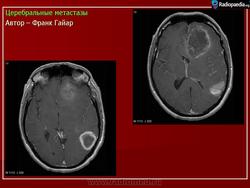

ГМ. Церебральные метастазы. +

Церебральные метастазы.